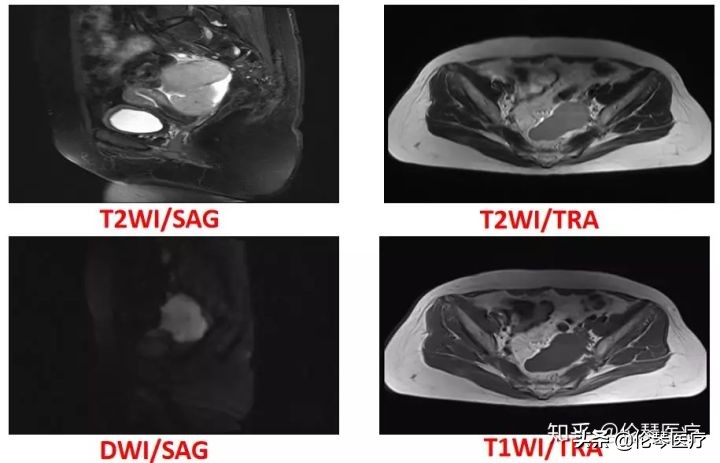

如图所示,患者左侧卵巢上有一个非常实性的肿瘤,在DWI上信号非常高,且在增强扫描中也有中度的强化,说明肿瘤细胞很致密,水分子在细胞间不容易运动,可以诊断为恶性肿瘤。实际上,该病例是一个输卵管癌。